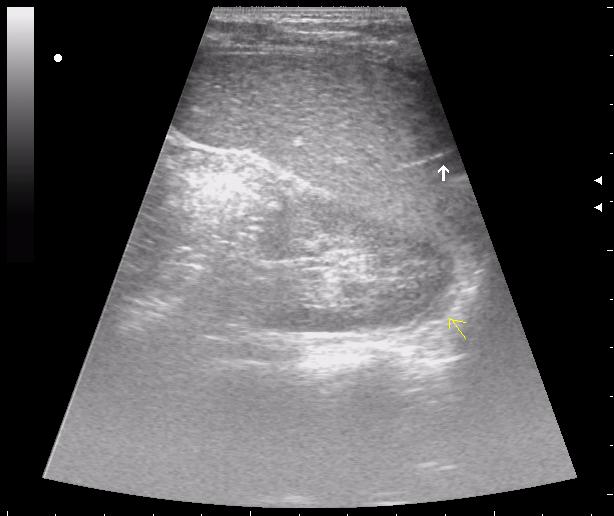

>желтой стрелкой - это левый надпочечник?

Похоже.

Он обычно располагается больше кнутри от верхнего полюса почки и может досигать ее ворот.

Надежнее визуализировать ЛН из позиции, которую я показывал в известной Вам теме.